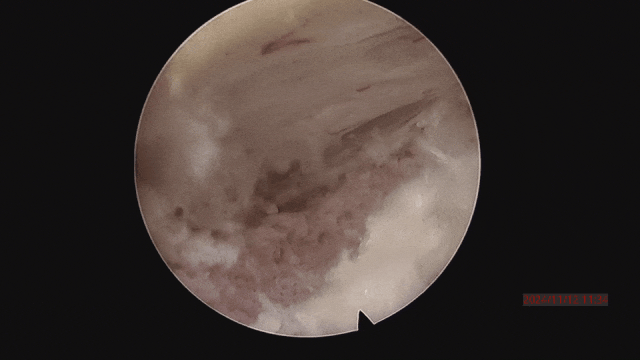

▲取骨塊后,解除神經壓迫。